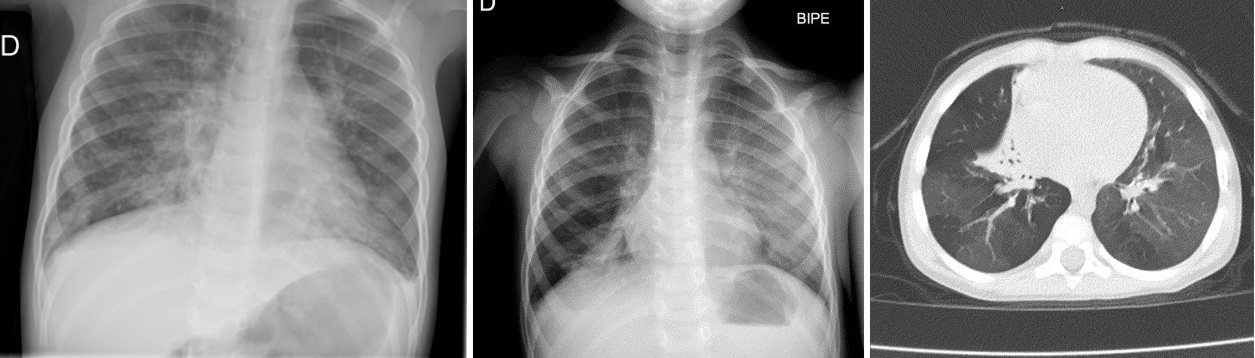

Se repite RxT, donde persiste atelectasia de lóbulo medio e hiperclaridad de lóbulo inferior derecho sugerente de atrapamiento aéreo, así como opacidad en vidrio deslustrado del parénquima pulmonar izquierdo, junto con varios episodios de sibilantes y crepitantes basales que no mejoran con corticoides sistémicos durante 1 mes.

Es en ese momento, ante alta sospecha de BOPI, cuando se decide realizar tomografía computarizada (TC) torácica que muestra patrón en mosaico bilateral, de predominio basal, atelectasia del lóbulo medio y atelectasias cilíndricas y subsegmentarias compatibles con bronquiolitis obliterante.

Radiografías de tórax y tomografía computarizada